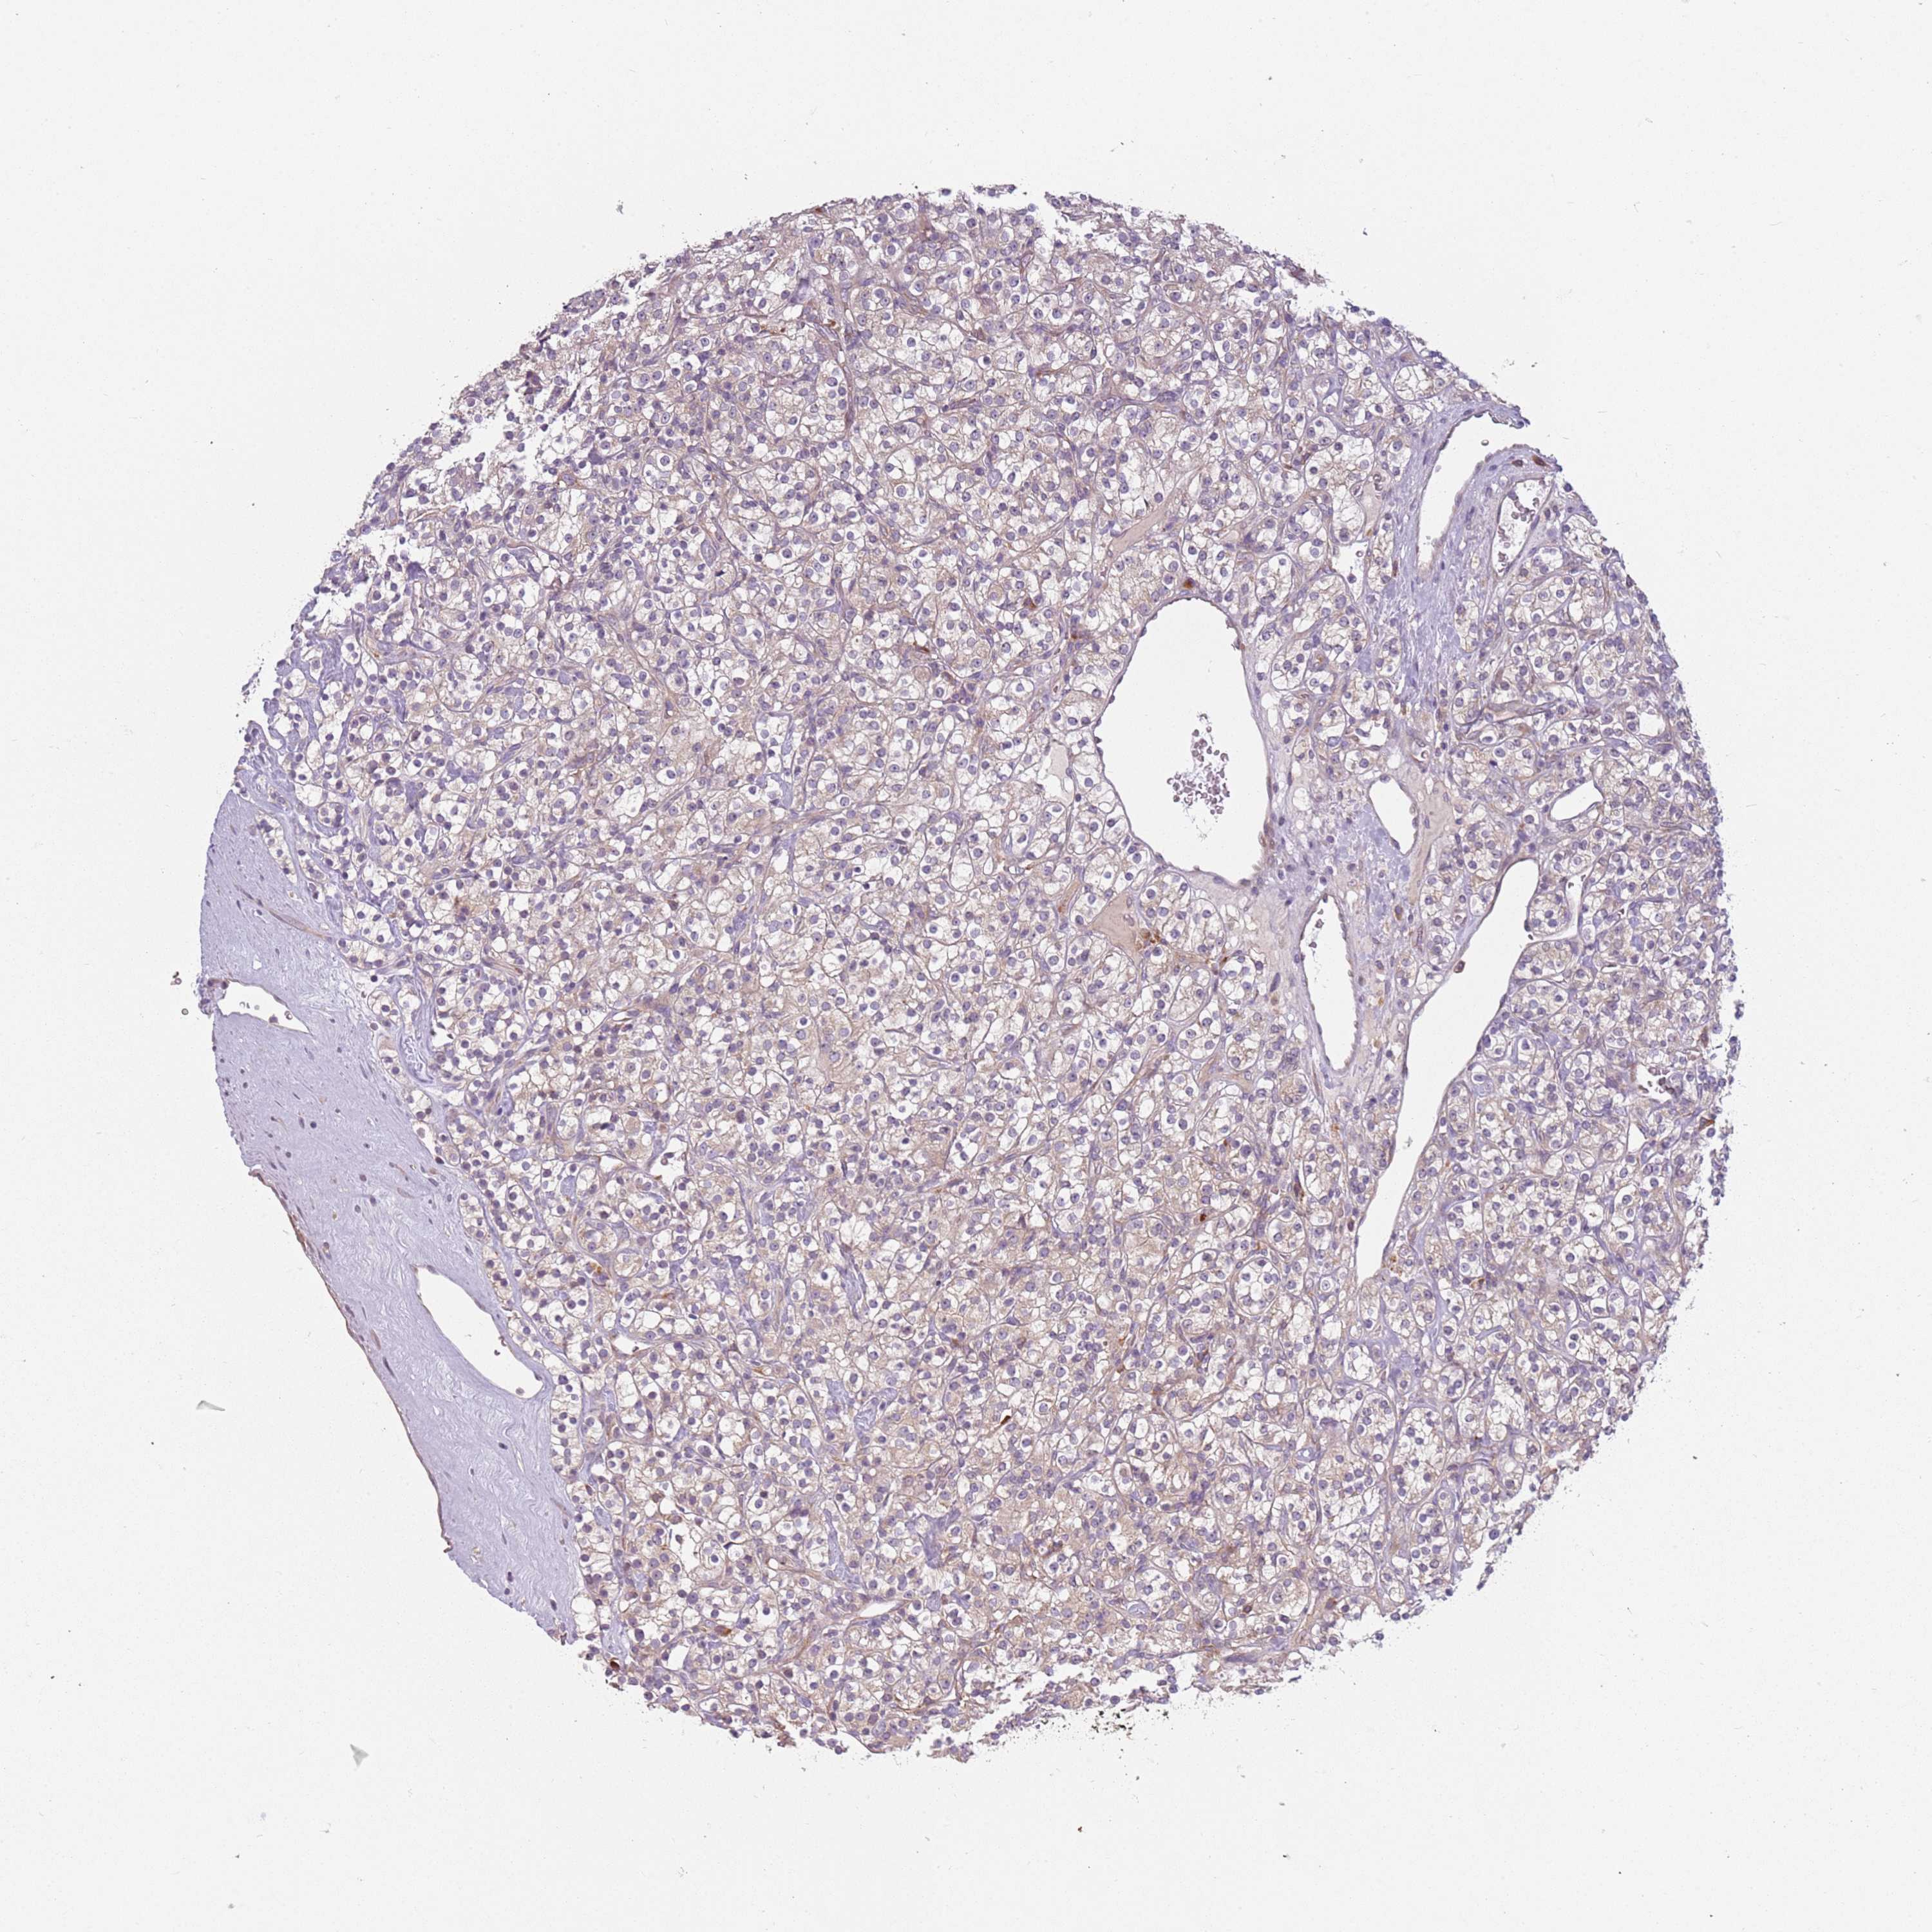

KIDNEY RENAL CLEAR CELL CARCINOMA (TCGA) - Interactive survival scatter ploti

The Survival Scatter plot shows the clinical status (i.e. dead or alive) for all individuals in the patient cohort, based on the same data that underlies the corresponding Kaplan-Meier plots. Patients that are alive at last time for follow-up are shown in blue and patients who have died during the study are shown in red.

The x-axis shows the expression levels (FPKM) of the investigated gene in the tumor tissue at the time of diagnosis. The y-axis shows the follow-up time after diagnosis (years). Both axes are complimented with kernel density curves demonstrating the data density over the axes. The top density plot shows the expression levels (FPKM) distribution among dead (red) and alive patients (blue). The right density plot shows the data density of the survived years of dead patients with high and low expression levels respectively, stratified using the cutoff indicated by the vertical dashed line through the Survival Scatter plot. This cutoff is automatically defined based on the FPKM cutoff that minimizes the p-score. The cutoff can be changed by dragging the vertical line or by entering a cutoff value in the square labeled "Current cut-off".

Under the Survival Scatter plot the p-score landscape (black curve; left axis) is shown together with dead median separation (red curve; right axis). Dead median separation is the difference in median mRNA expression between patients who have died with high and low expression, respectively. It is calculated as follows: median FPKM expression of dead patients with high expression - median FPKM expression of dead patients with low expression. This is intended to aid the user in visually exploring custom cutoffs and the associated p-scores and dead median separation.

Individual patient data is displayed and can be filtered by clicking on one or more of the category buttons on the top of the page. Categories describing expression level and patient information include: high, low, alive, dead, female, male and tumor stages. The scale of the x-axis can be toggled between linear and log-scale by clicking on the "x log" button. Mouse-over function shows TCGA ID, patient information and mRNA expression (FPKM) for each patient.

& Survival analysisi

Kaplan-Meier plots summarize results from analysis of correlation between mRNA expression level and patient survival. Patients were divided based on level of expression into one of the two groups "low" (under cut off) or "high" (over cut off). X-axis shows time for survival (years) and y-axis shows the probability of survival, where 1.0 corresponds to 100 percent.

RPS28 is potential prognostic, high expression is favorable in Kidney Renal Clear Cell Carcinoma (TCGA)

: 134.83

Average pTPM 195.4

Number of samples 521